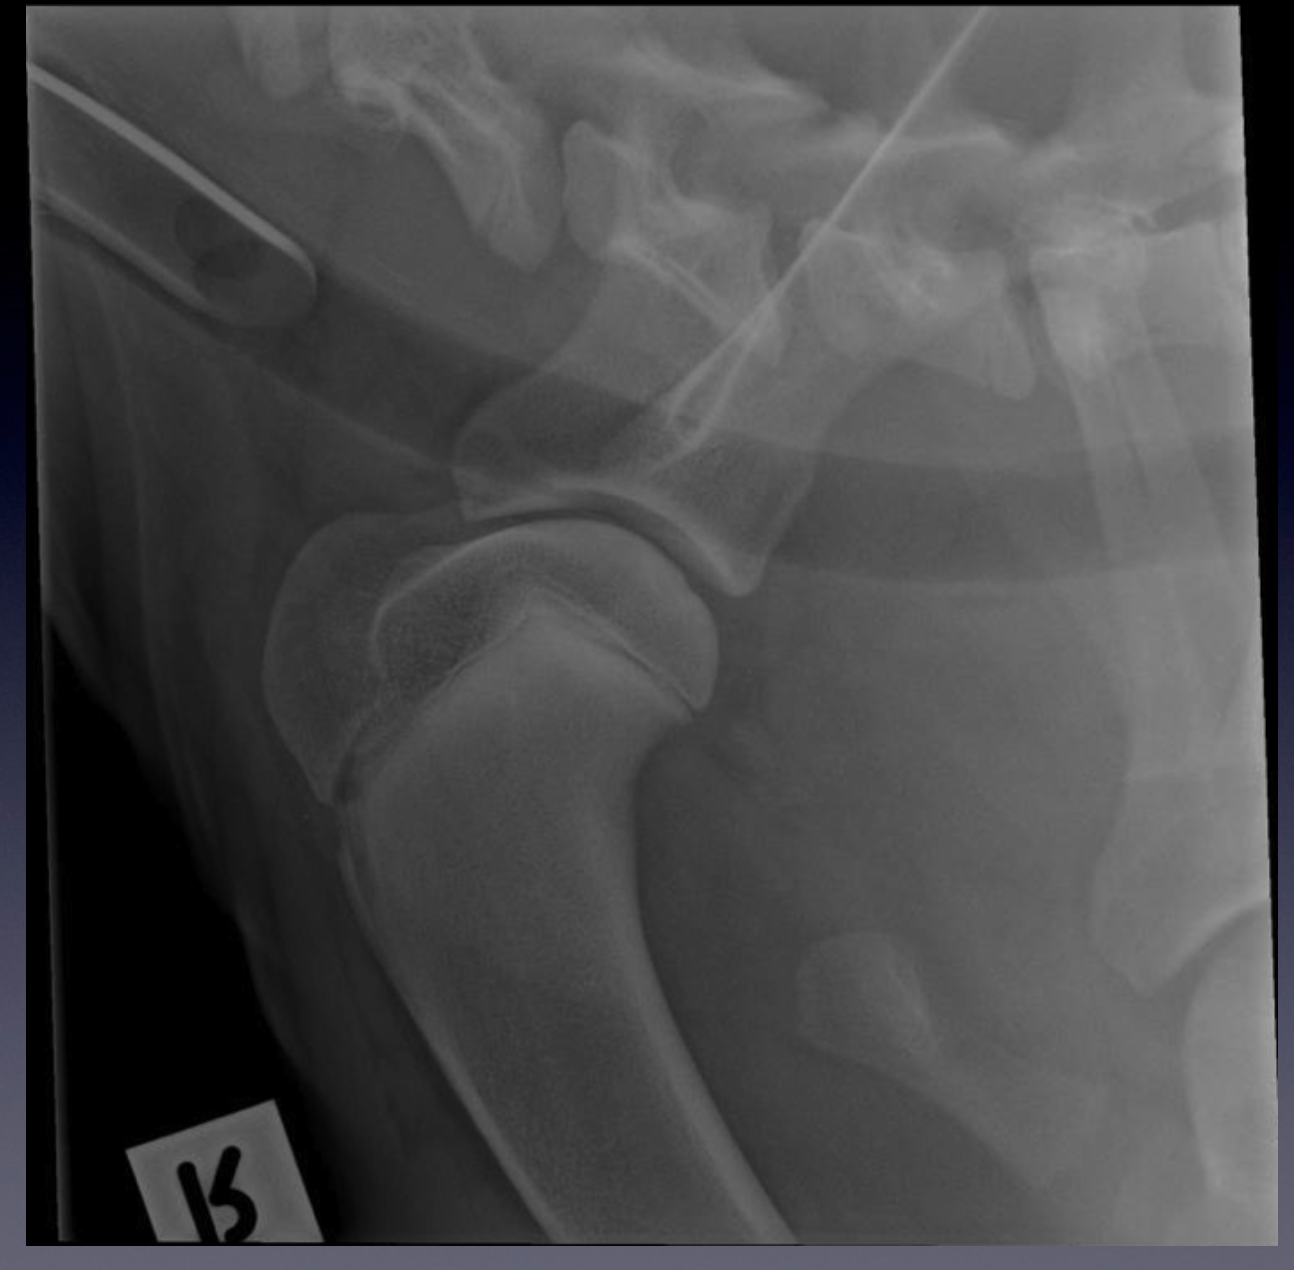

Case 4: Patient 246004

VIEW? Mature?

Please note the presence of an endotracheal tube indicating the dog is anaesthetised.

Irregular contour of the articular surface of the humeral head, with a defect present in

the caudal aspect of the articular surface.

Underlying this defect there is increased bone opacity indicating sclerosis of the

subchondral bone.

These findings are typical for osteochondrosis of the shoulder in dogs. A cartilage flap

or nom-mineralised joint mice can only be detected radiographically, using arthrography

ie. injecting iodinated contrast medium into the shoulder joint.

Mediolateral projection of the shoulder of a skeletally immature dog.